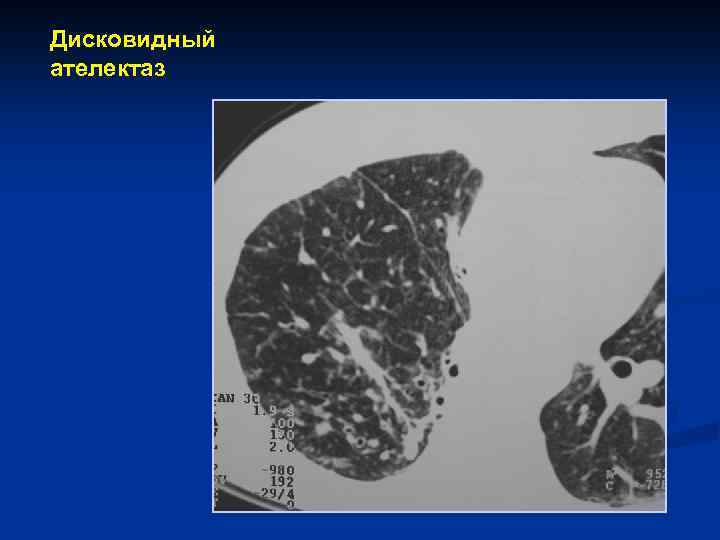

Осложнения пневмоний n n n Экссудативный плеврит Эмпиема плевры Абсцедирование (присоединение гноеродной флоры, нарушение кровообращения и проходимости мелких бронхов, чаще при стафилококковой пневмонии через 5 -7 дней от начала) Сепсис Диафрагматит (утолщение купола, его высокое расположение, нечеткость, неровность контура) Дисковидный коллапс (ателектаз) – рефлекторная реакция на воспаление. Имеет вид тяжа, переходит на соседний сегмент

Дисковидный ателектаз